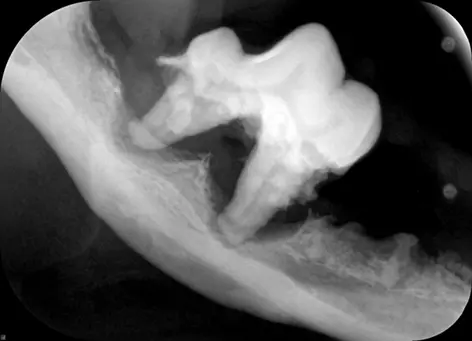

Once asleep we will x-ray all the teeth. This, in combination with an anesthetized dental exam, tells us which teeth need extraction because disease is too far progressed and which teeth are healthy enough to stay.